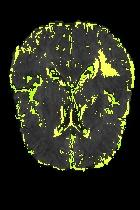

Current unsupervised anomaly localization approaches rely on generative models to learn the distribution of normal images, which is later used to identify potential anomalous regions derived from errors on the reconstructed images. However, a main limitation of nearly all prior literature is the need of employing anomalous images to set a class-specific threshold to locate the anomalies. This limits their usability in realistic scenarios, where only normal data is typically accessible. Despite this major drawback, only a handful of works have addressed this limitation, by integrating supervision on attention maps during training. In this work, we propose a novel formulation that does not require accessing images with abnormalities to define the threshold. Furthermore, and in contrast to very recent work, the proposed constraint is formulated in a more principled manner, leveraging well-known knowledge in constrained optimization. In particular, the equality constraint on the attention maps in prior work is replaced by an inequality constraint, which allows more flexibility. In addition, to address the limitations of penalty-based functions we employ an extension of the popular log-barrier methods to handle the constraint. Comprehensive experiments on the popular BRATS'19 dataset demonstrate that the proposed approach substantially outperforms relevant literature, establishing new state-of-the-art results for unsupervised lesion segmentation.